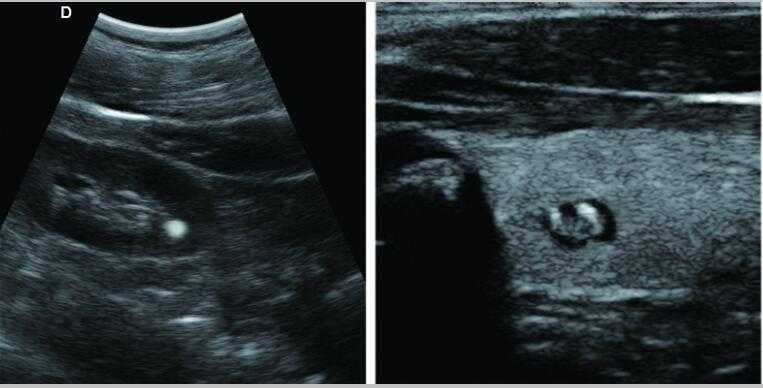

7.應用:腹部、婦科、產科、心臟、血管和小器官、泌尿科、肌肉骨骼、兒科等

本設備不適用于含氣臟器如肺等臟器的檢查。建議不要對有創口或急性炎癥部位進行探查,以免交叉感染。下列患者禁用陰道和直腸探頭:陰道炎癥,如滴蟲性陰道炎、霉菌性陰道炎、性病等;未婚者;陰道畸形者;月經期;絕經后陰道萎縮;陰道超聲檢查困難者;陰道出血; 前置胎盤患者等。以下患者禁用穿刺:高血壓,冠心病,有凝血障礙和出血傾向的患者。